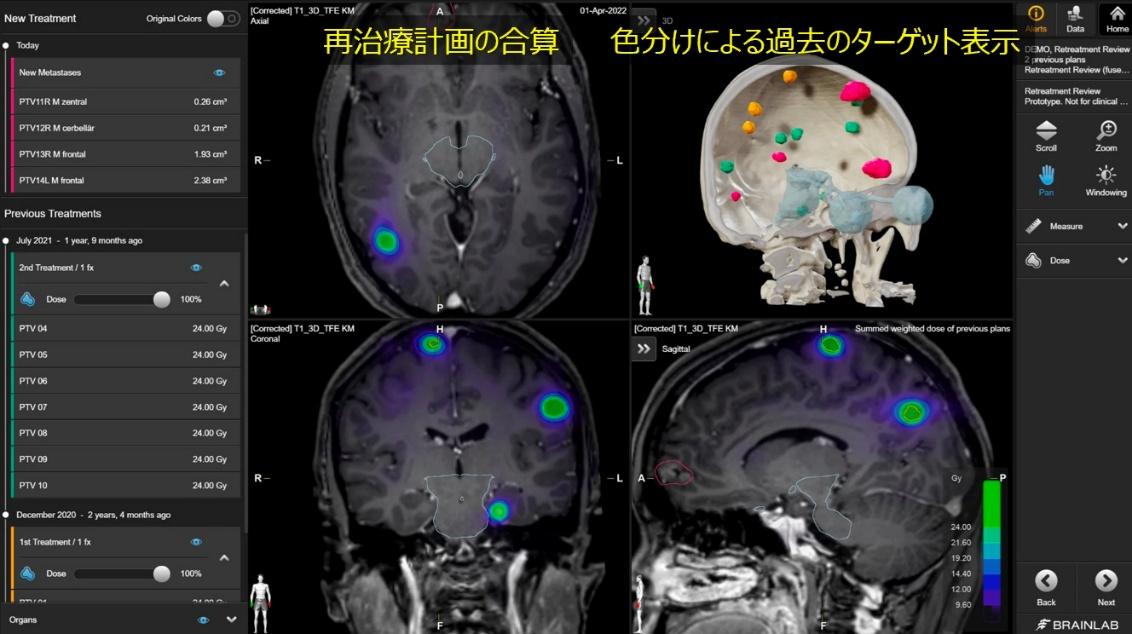

再治療計画専用ソフトウェア(Elements Retreatment)

Elements Retreatment は、過去に放射線治療を受けた部位に対して再度治療を行う際に、安全に治療計画を作成するための支援ソフトウェアです。放射線治療では、一度照射した臓器や正常組織にどの程度の線量が既に与えられているかを考慮することが非常に重要です。

Elements Retreatment では、過去の治療計画データと現在の画像データを統合し、以前の照射で受けた線量分布を現在の治療計画に重ねて評価することができます。これにより、正常組織に蓄積される放射線量を確認しながら、新たな治療計画を作成することが可能です。

この機能により、再照射が必要となる症例においても、安全性に配慮しながら適切な線量設計を行うことができ、患者さん一人ひとりの状況に応じた、より慎重で精度の高い放射線治療につながります。